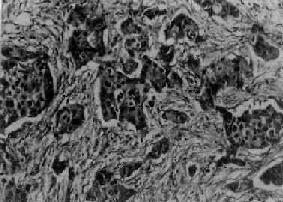

图13-27 乳腺髓样癌

癌细胞排列成片团状,间质少